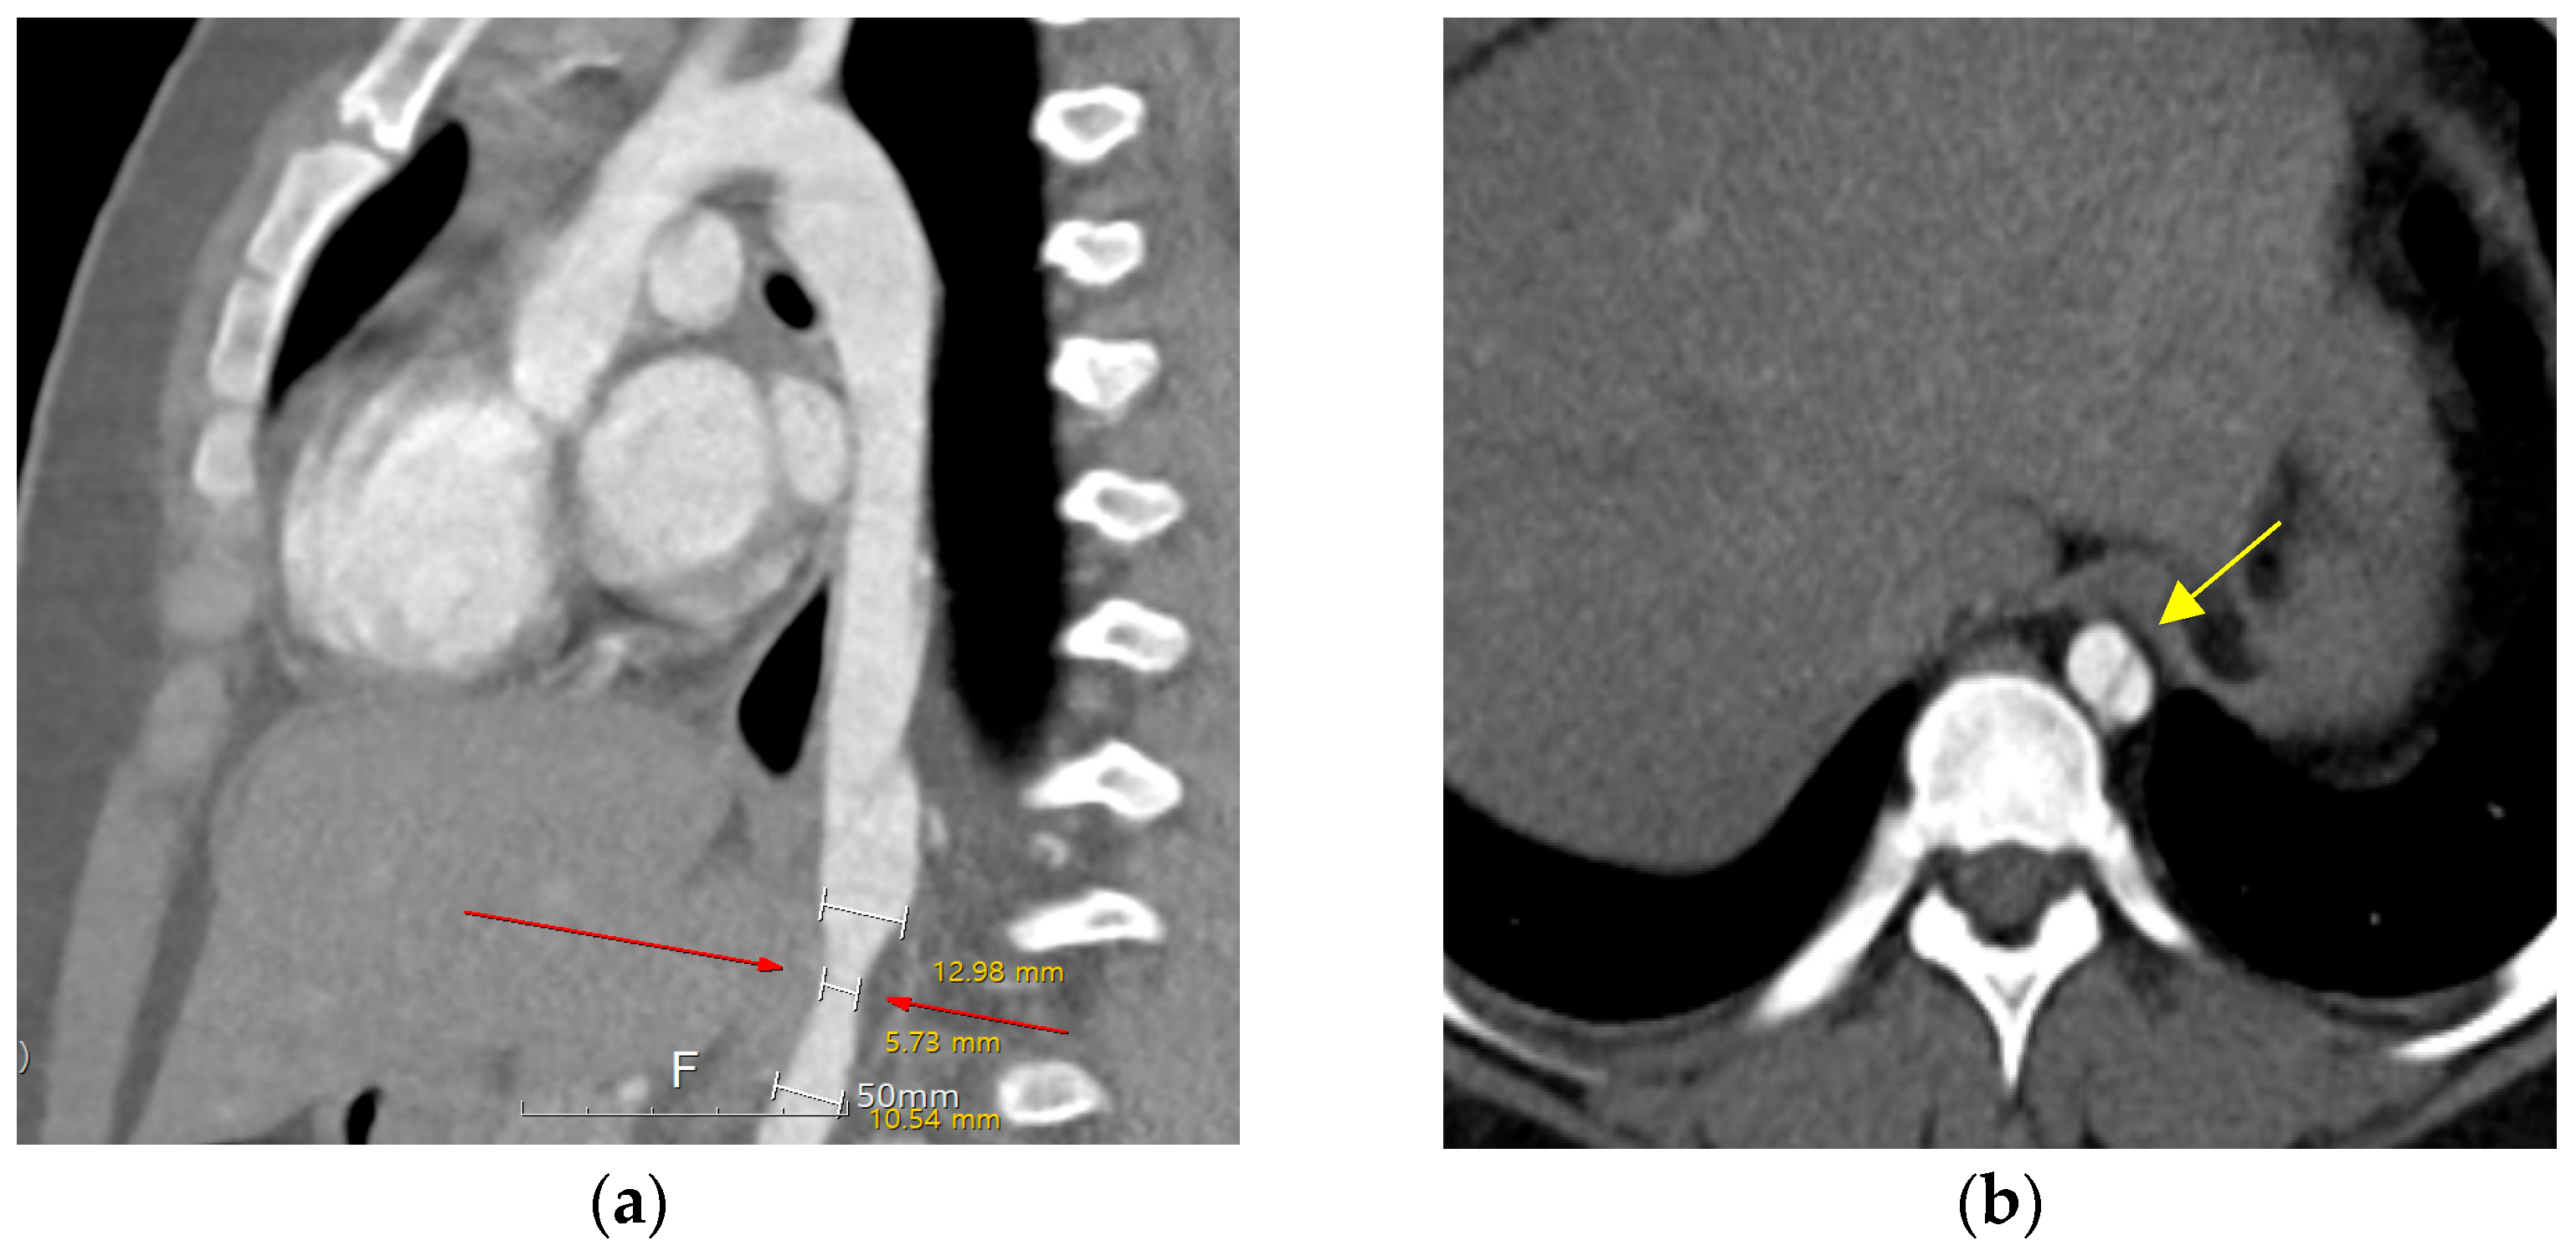

Ten years after the percutaneous PDA closure, limb blood pressure (BP) discrepancies were noted at the outpatient clinic (upper/extremity [U/E] 162/49 mmHg and lower/extremity [L/E] 131/100 mmHg). The patient was 11 years old, weighed 70 kg, and was 147 cm in height. The echocardiographic findings were as follows: closed PDA with mild aortic regurgitation and obstruction of the abdominal aorta with a Vmax of 2.5 m/s (maximum trans-stenotic pressure gradient of 27 mmHg). Left ventricular function was normal, with an ejection fraction of 64%. Chest radiography was nonspecific, and electrocardiography showed a normal sinus rhythm without specificity. Computed tomography (CT) further confirmed a dissecting descending aorta from T8 to T9 with complete luminal collapse and focal stenosis of the distal descending aorta at the T10 level. The diameter of the descending aorta was 12.9 mm in the upper portion, 5.7 mm in the stenotic portion, and 10.5 mm in the lower portion (Figure 1). Renal function test results remained within the normal ranges.

Figure 1. Aorta, abdominal CT. (a) Sagittal view, dissection of descending aorta. Focal stenosis at the distal descending aorta at the T10 level (red arrow). (b) Axial view, true lumen, and false lumen with intimal flap at T8–9 level (yellow arrow).